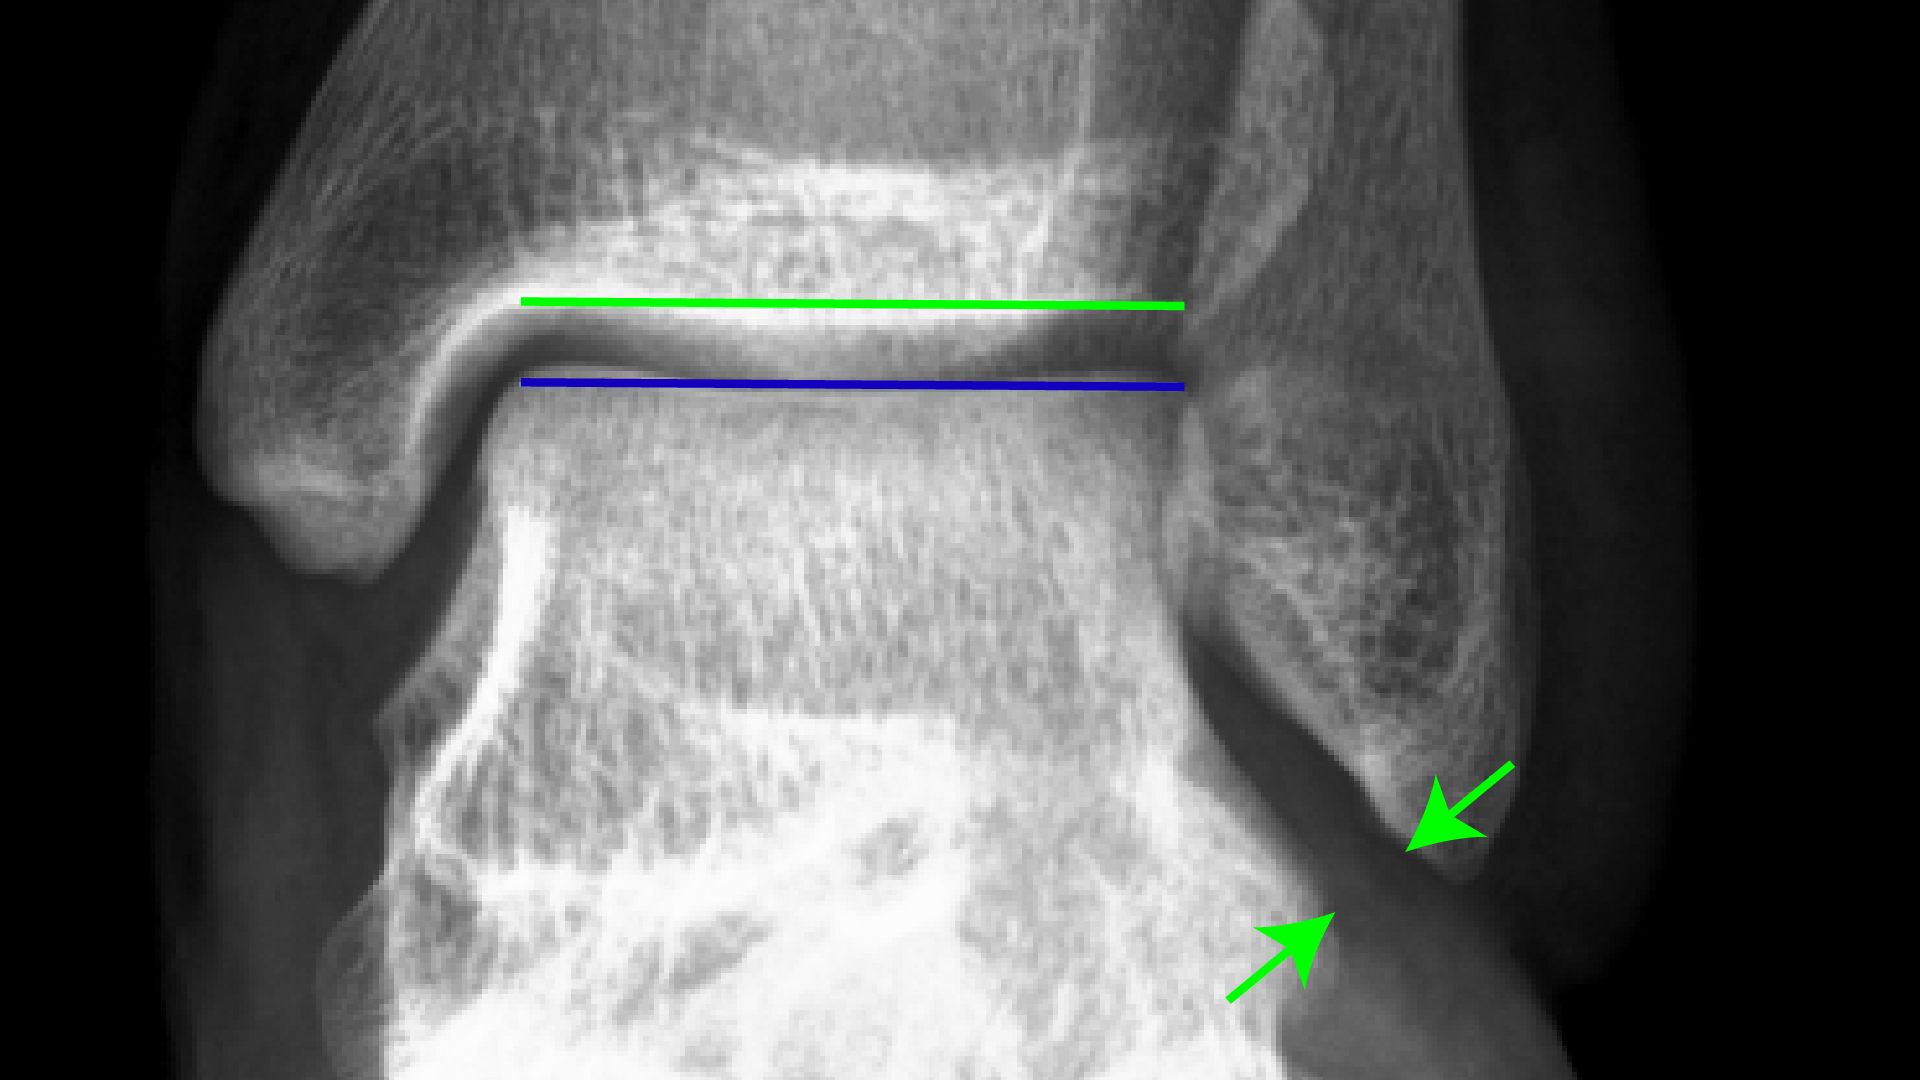

Normal values at standard Xray views (AP,Mortise and lateral)of the Ankle Injury X Ray Criteria This acr appropriateness criteria defines best practices for imaging evaluation for several variants of patients presenting with. Recommend ankle radiographs in patients with the following clinical criteria in the acute setting: 1) inability to bear weight, 2) point tenderness. Ankle Injury X Ray Criteria.

Mortise and Lateral View Xray of Left Ankle. Mortise and lateral view Ankle Injury X Ray Criteria 1) inability to bear weight, 2) point tenderness. Recommend ankle radiographs in patients with the following clinical criteria in the acute setting: This acr appropriateness criteria defines best practices for imaging evaluation for several variants of patients presenting with. Ankle Injury X Ray Criteria.

Plain xray mortise view of the right ankle showing syndesmotic ankle Ankle Injury X Ray Criteria Recommend ankle radiographs in patients with the following clinical criteria in the acute setting: This acr appropriateness criteria defines best practices for imaging evaluation for several variants of patients presenting with. 1) inability to bear weight, 2) point tenderness. Ankle Injury X Ray Criteria.

Plain xray AP Lateral views of the right ankle showing syndesmotic Ankle Injury X Ray Criteria 1) inability to bear weight, 2) point tenderness. Recommend ankle radiographs in patients with the following clinical criteria in the acute setting: This acr appropriateness criteria defines best practices for imaging evaluation for several variants of patients presenting with. Ankle Injury X Ray Criteria.